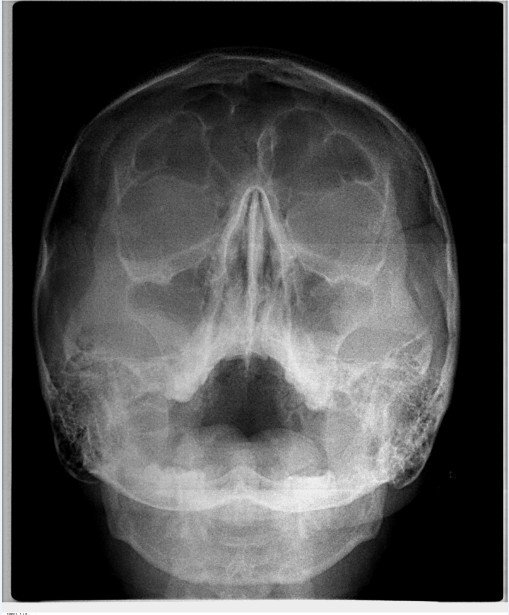

На верхней челюсти справа в районе зуба 6 образовалась небольшая припухлость, которая видна только со стороны щеки, при постукивании на сам зуб отдает болью, десна вокруг зуба не красная и не припухлая, воспаленной не выглядит, зуб залеченный.

Сделали снимок, врач, делавший снимок, направляет на удаление зуба по результатам снимка.